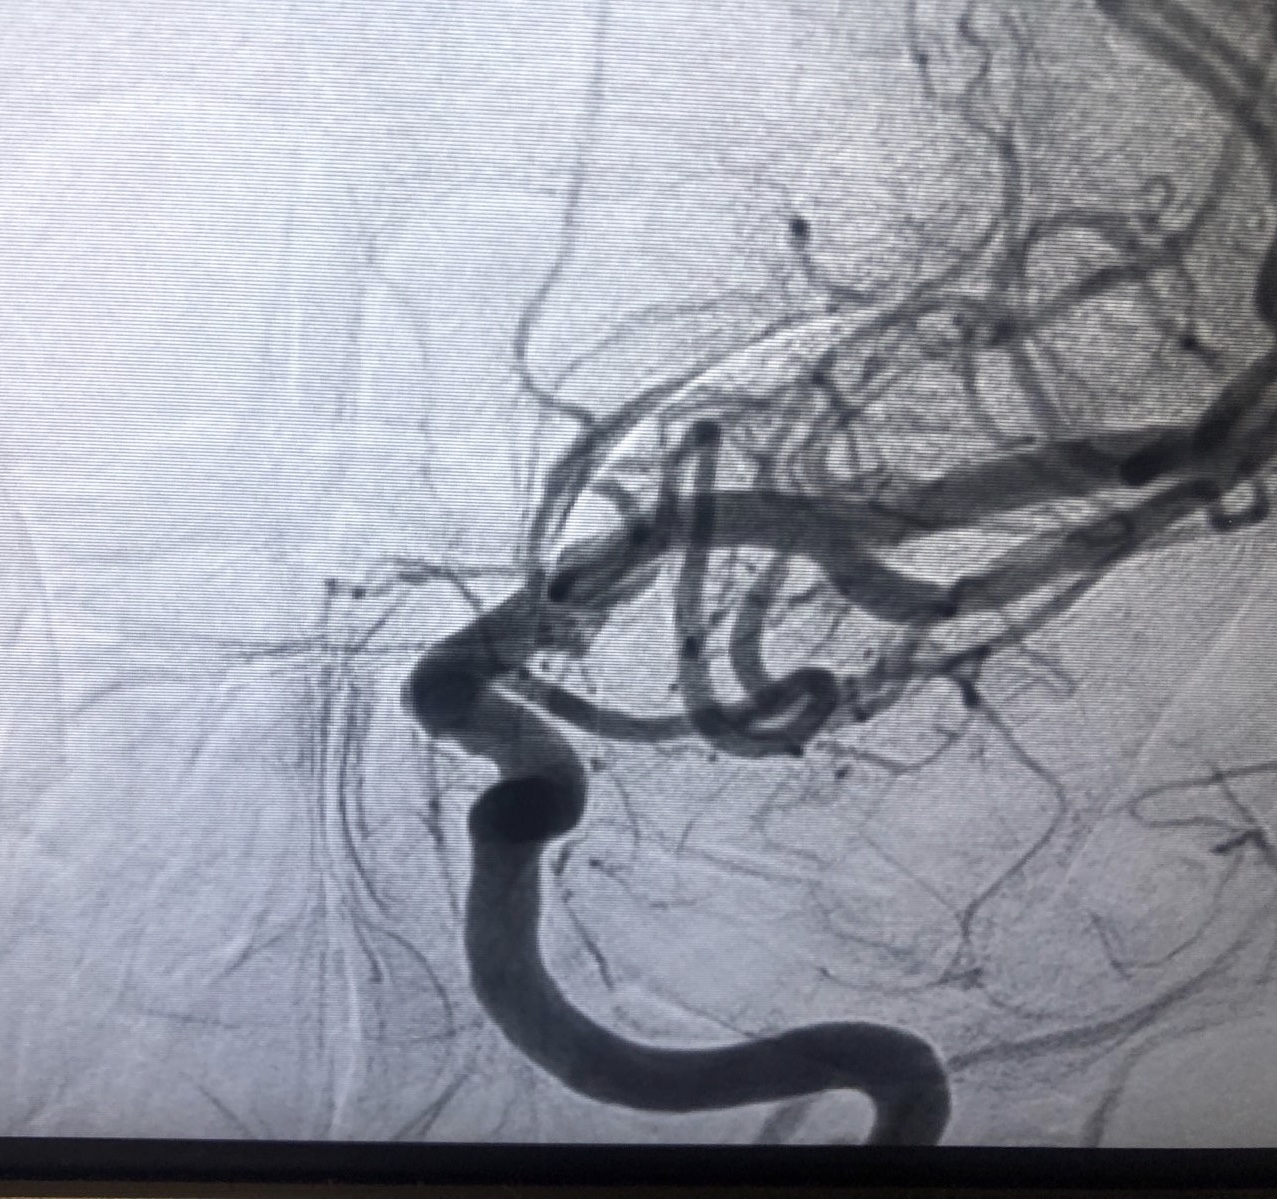

Pre-stent and post-stent images of blood flow (note the extremely limited blood flow – parts of the artery are nearly separated) in image 1 compared to image 2).

Angioplasty was not enough so they placed a 2mm x 8mm cobalt chromium stent. Dr. Perl looked extremely worried when I made a sound in response to the stent placement. After he finished he said “well it wasn’t your day to meet the celestial beings.” My speech immediately improved.

What I didn’t know is that Dr. Perl told Sara he did not expect me to survive. Blood flow was extremely restricted. I wish I could have spared Sara and Liz and all my loved ones the worry this caused.

Just after surgery Dr. Perl showed me images of my brain on his phone (the images at the beginning of this post). The next morning I asked him if he’d be willing to share the “super sexy pictures of my brain” and he texted me the images. This map of my stroke is based on those images:

Red areas show blood flow pre-stent. The small sliver of red in the center of the collapse shows the bridge of blood that kept me alive. Blue areas did not experience flow during the stroke. They are a catalogue of damage.